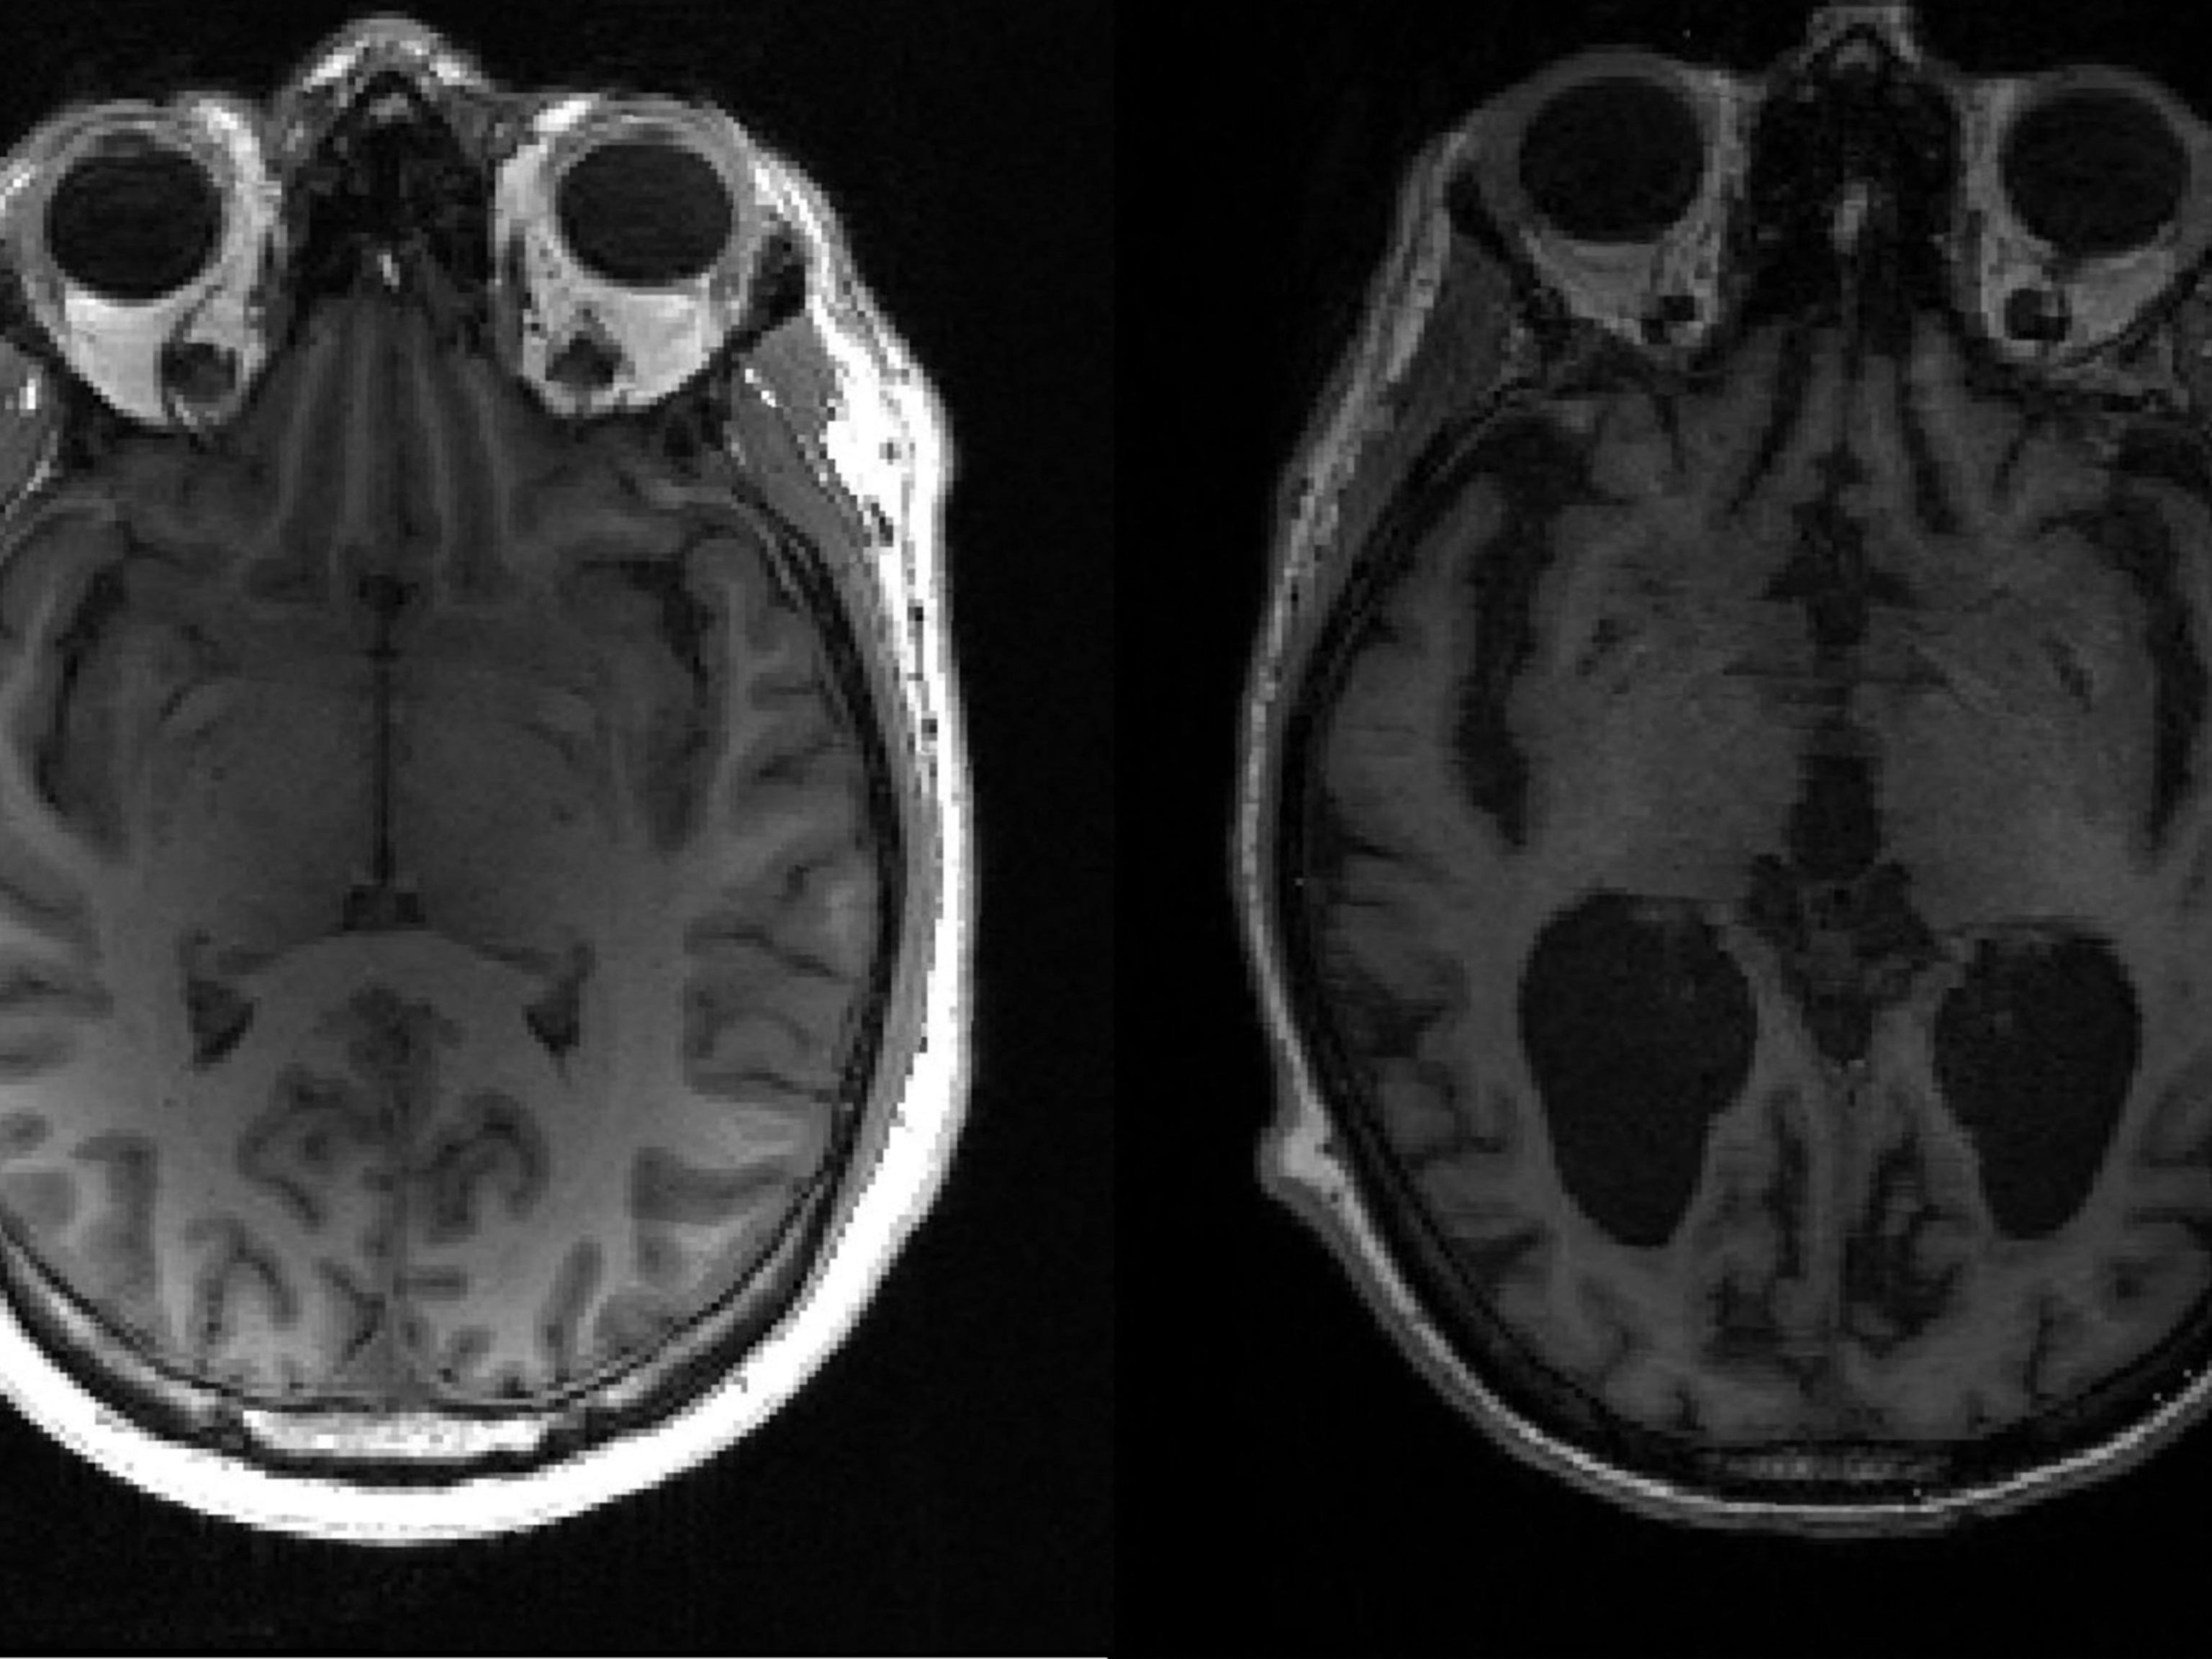

20 Jahre von den ersten Veränderungen bis zu Demenz-Problemen

Eventuell könnten diese monoklonalen Antikörper in früheren Stadion gut eingesetzt werden, meint der Mediziner: Es dauert 20 Jahre von den ersten Veränderungen im Gehirn bis das Organ so stark geschädigt ist, dass die Patienten Probleme haben. Wenn man während dieser Zeit die schädlichen Eiweiß-Ablagerungen im Gehirn verhindern kann, kommt es vielleicht gar nicht zu ernsthaften Krankheitszeichen.